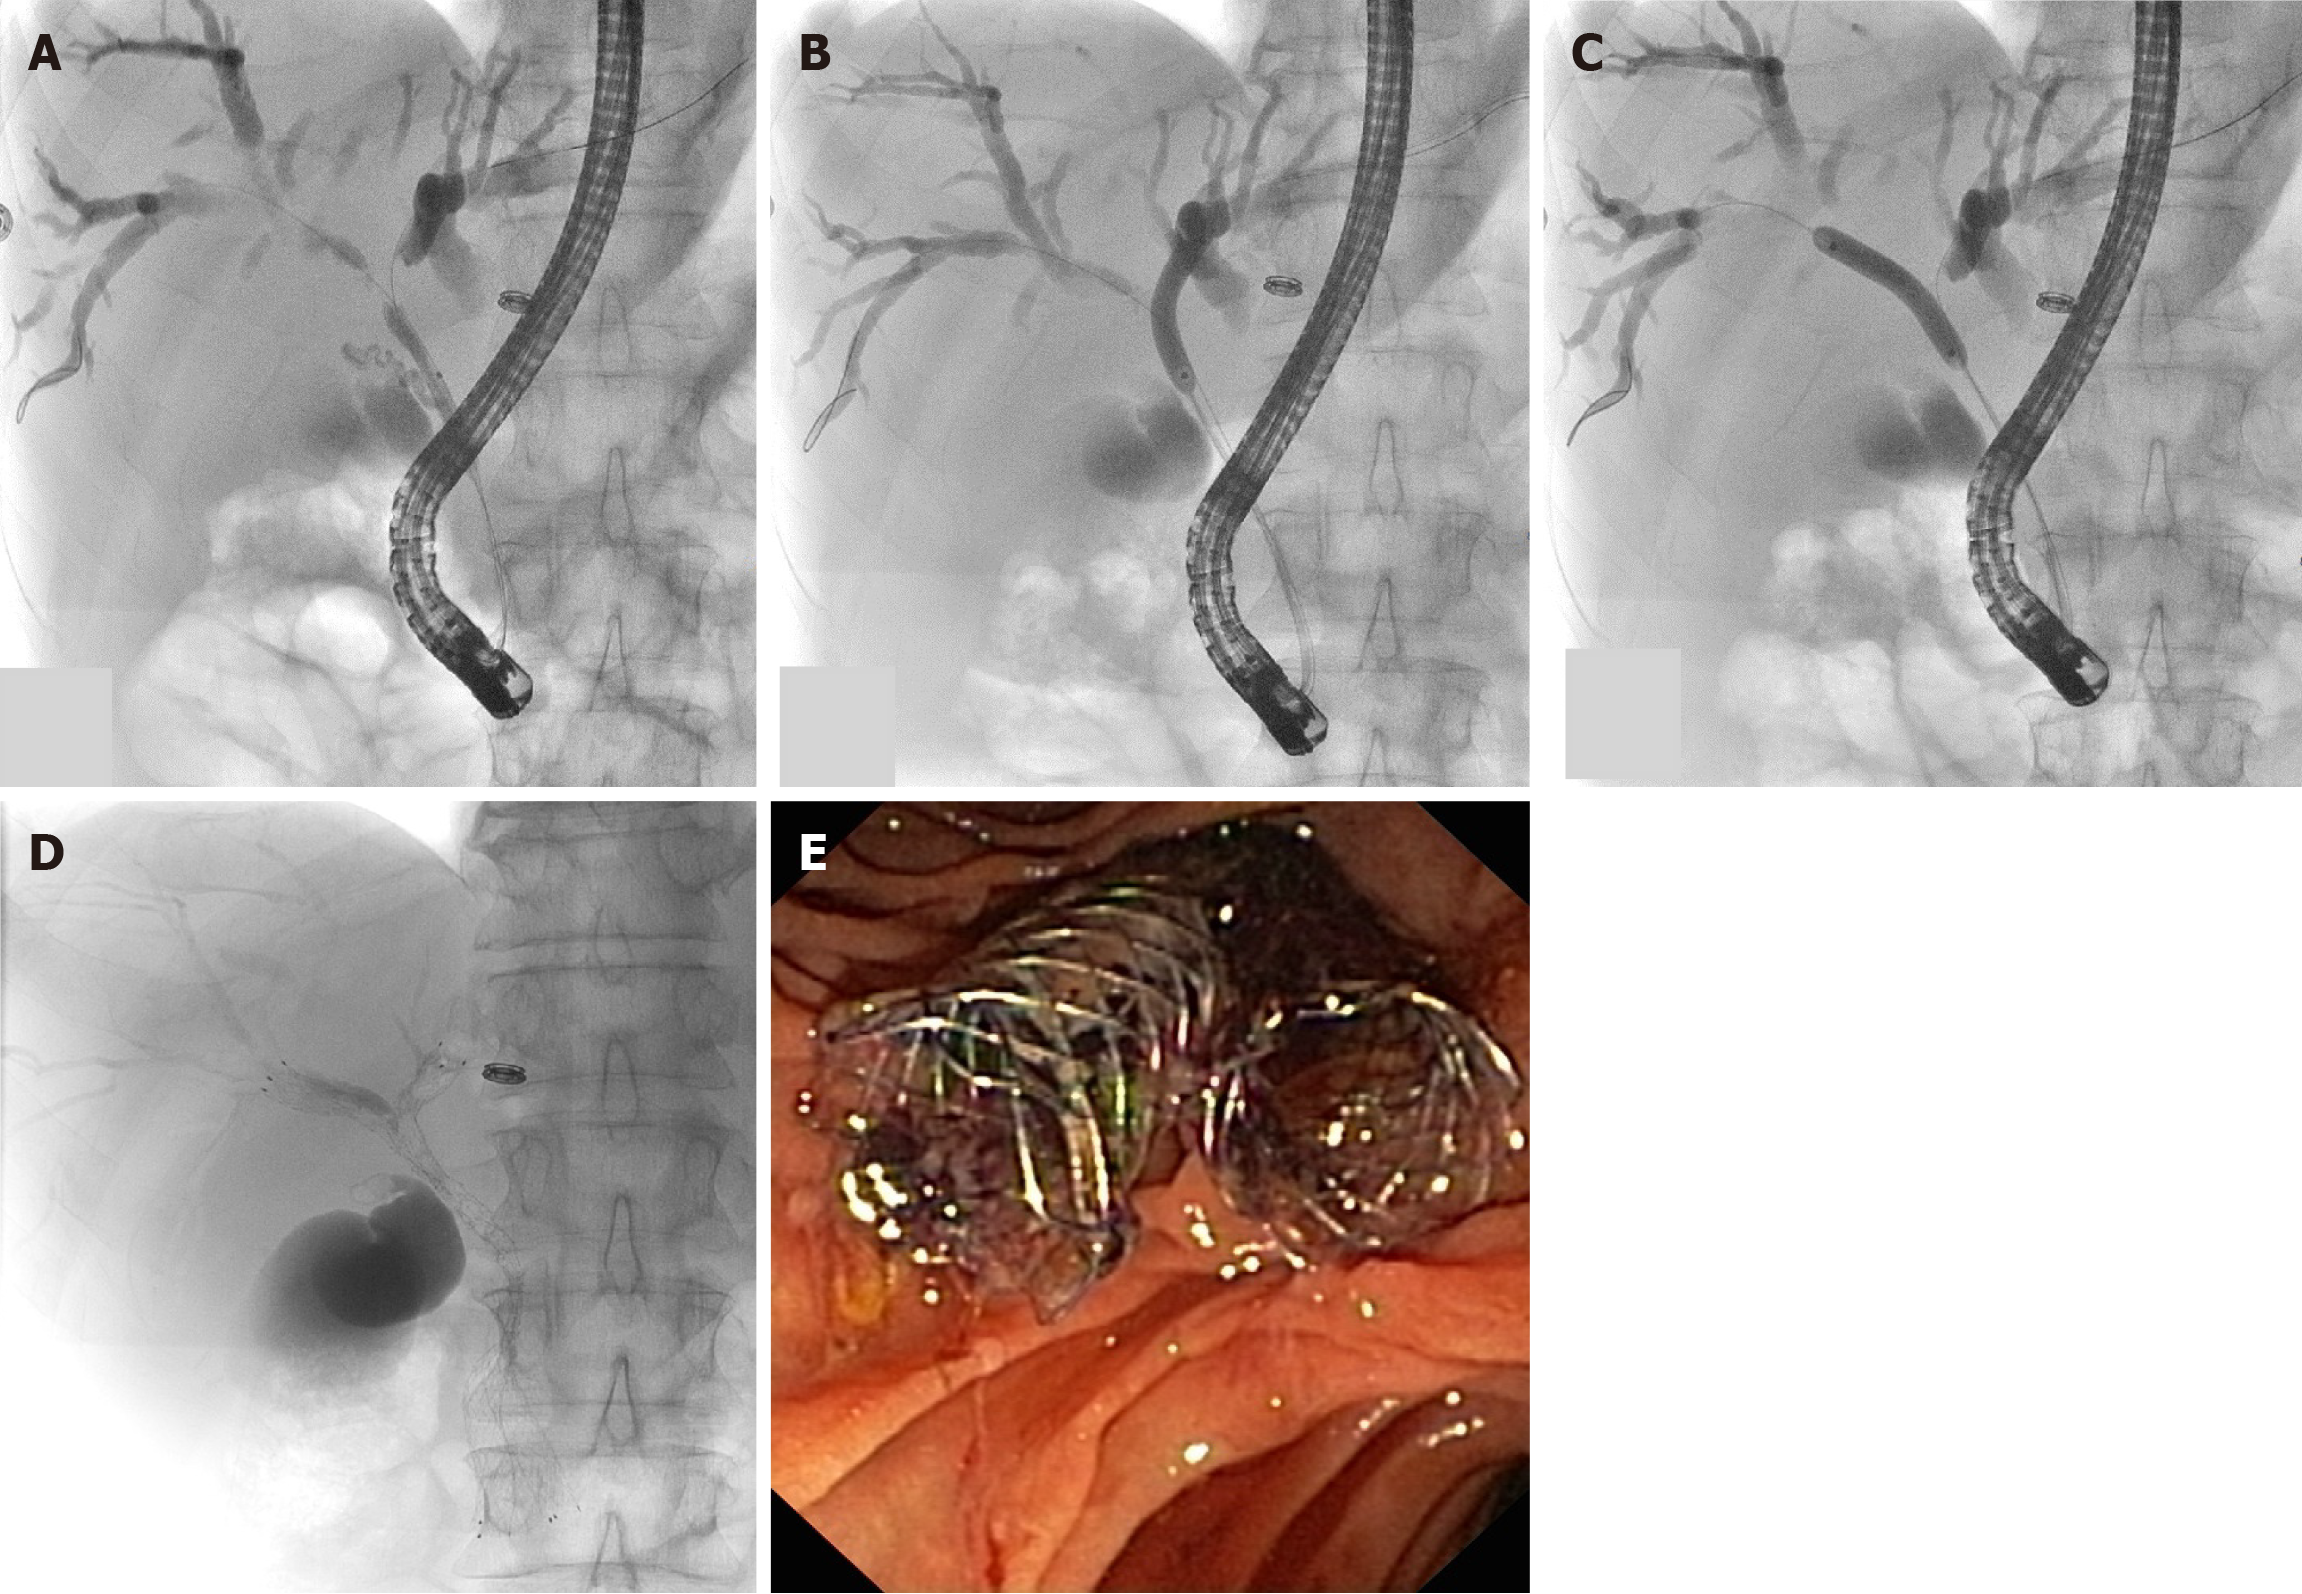

Figure 1

Sequential stent in stent bilateral drainage on X-ray view.